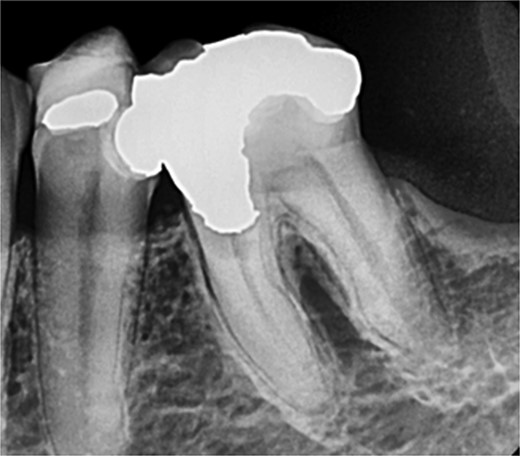

A 44-year-old patient presented to our clinic with the primary complaint of food lodgment in a cavity on the lower left posterior teeth. Clinical examination revealed extensive caries on the disto-occlusal surface of the lower left first permanent molar (tooth 36) (Fig. 1). Radiographic examination showed a large radiolucency at the distal crown extending to the cervical third of the distal root, with periapical radiolucencies on both mesial and distal roots (Fig. 2). The tooth was diagnosed with asymptomatic irreversible pulpitis and symptomatic apical periodontitis.

Periapical radiograph of tooth 36 showing a large radiolucency area at the distal crown involving the cervical third of the distal root.